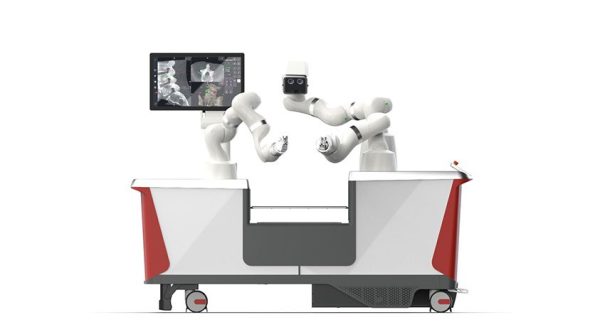

The successful procedures demonstrated the precision and efficiency of the Dynamis platform in a live clinical setting.

The study confirms the safety, usability, and intraoperative performance of the device across 30 patients treated in Germany.